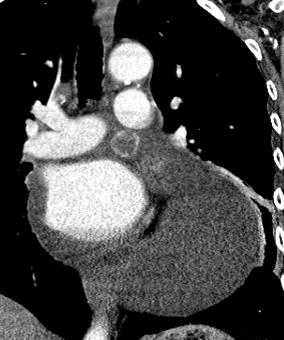

Cardiothoracic surgery was contacted for a pericardial window and biopsy. A repeat contrast enhanced chest CT scan suggested an 18 x 16 mm peripherally enhancing intrapericardial mass, with central low attenuation between the main pulmonary artery and the left atrial appendage. The pericardial effusion was massive, the pericardium was mildly thickened, and a right apical 3 mm pulmonary nodule was evident (Fig. 3).